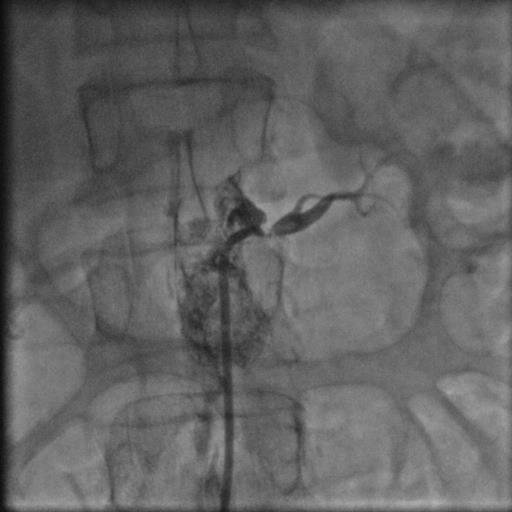

44 yaşında şeker hastalığı olan hastamız dirençli yüksek tansiyon şikayetiyle bize başvurdu. Herhangi bir sebep bulunamayan hastamız 2 yıldan beri cesitli ilaçlar kullanmasına rağmen tansiyonunun düşürülemediğini söylüyordu. Yaptiğımız detaylı muayene ve tetkikler sonucu böbrek damarının tıkalı olduğunu tesbit ettik ve yaptıgımız stent işlemi sonrasında hastamız normal tansiyon değerleriyle taburcu edildi..